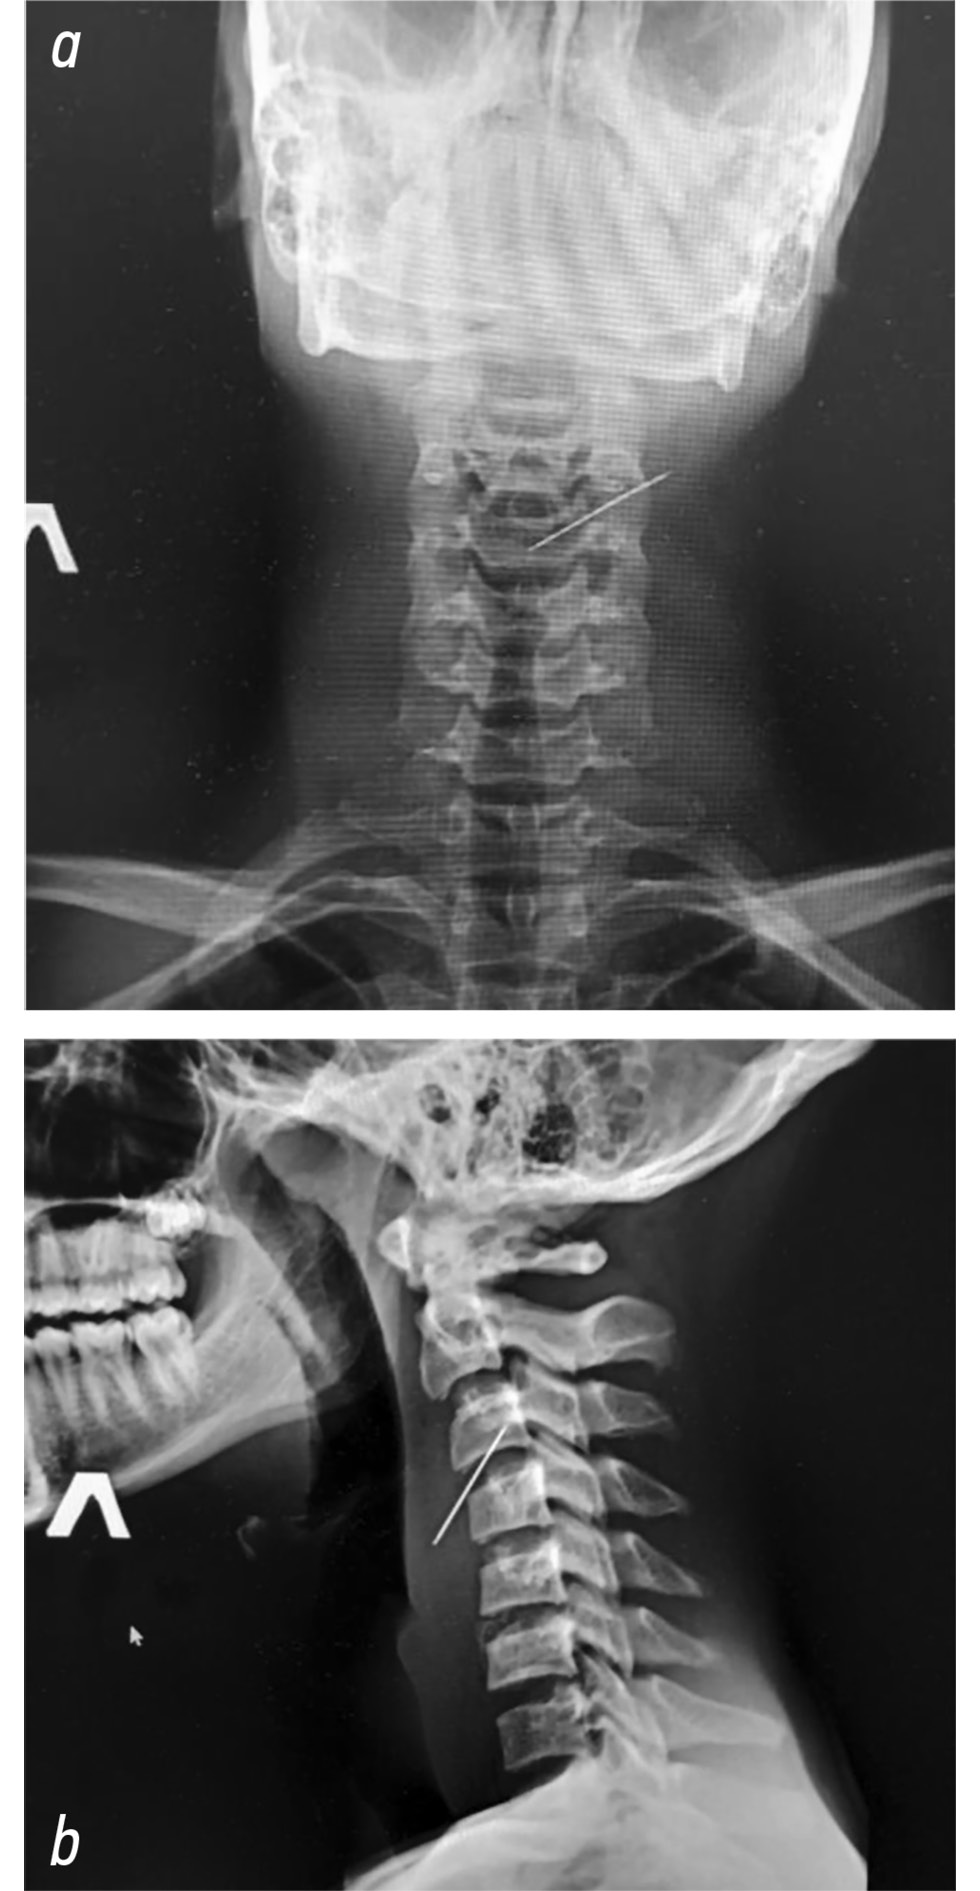

При осмотре определяется, что вязальная спица прошла справа по переднебоковой поверхности шеи в косо-восходящем направлении (рис. 1). При пальпации отмечается болезненность. Конец спицы определяется под кожей левой половины шеи без признаков кровотечения и подкожной эмфиземы (рис. 2). На рентгенограмме шейного отдела позвоночника определяется тень металлического инородного тела (спица), проходящая в косо-восходящем направлении справа налево в проекции от СVI до СVII (рис. 3, a, b).

Рис. 3. Рентгенограмма шейного отдела позвоночника: тень металлического инородного тела (спица), проходящая в косо- восходящем направлении (a — прямая, b — боковая проекция).

Fig. 3. Cervical spine x-ray: shadow of a metallic foreign body (pin), passing in the obliquely ascending direction (a — direct projection, b — lateral projection).